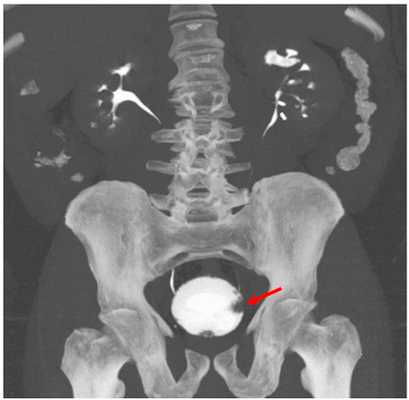

Рисунок. Магнитно-резонансная томография.

Рисунок. Рак мочевого пузыря на стадии T2b, с инвазией в мышечный слой.

Магнитно-резонансная томография особенно полезна в определении того, насколько далеко опухоль распространилась за пределы мочевого пузыря.